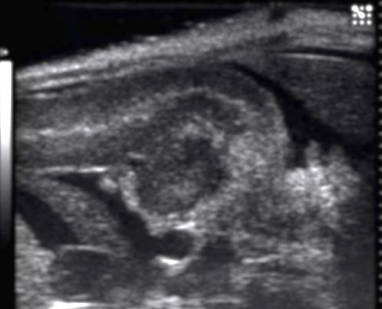

Acute pancreatitis with stone obstructing the pancreatic duct

Describe this image

Diagnosis?

Gallbladder with wall thickening and a stone obstructing the common bile duct causing dilatation (posterior shadowing). Results in pancreatitis

Dx: gallstones/pancreatitis